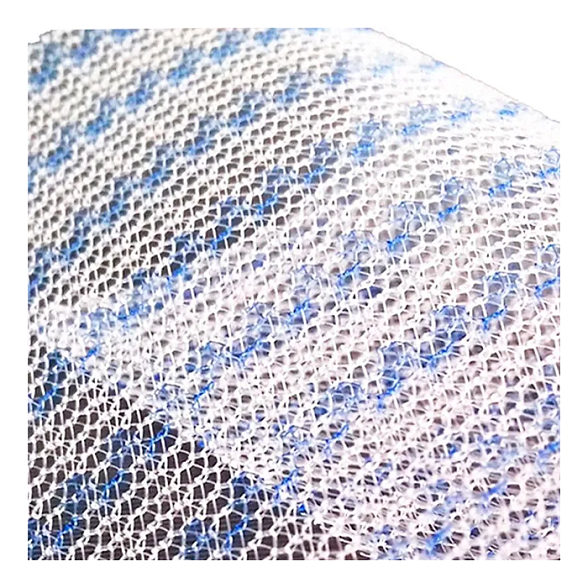

Эндопротез-сетка (сетка хирургическая) полипропиленовый для восстановительной хирургии ЭСФИЛ лёгкий, 15х10 см, Линтекс

Эндопротез-сетка полипропиленовая ЭСФИЛ лёгкий для восстановительной хирургии

Полипропиленовая хирургическая сетка ЭСФИЛ лёгкий от компании «Линтекс» — это современный высокотехнологичный имплантат, предназначенный для надежного и долговечного восстановления анатомических структур при пластических и реконструктивных операциях. Изделие специально разработано для хирургов, ценящих в работе баланс между прочностью, биосовместимостью и комфортом пациента в послеоперационном периоде.

Сетка ЭСФИЛ лёгкий представляет собой монофиламентное полипропиленовое полотно с облегченной структурой. Её ключевая особенность — оптимальное соотношение массы и прочности, что минимизирует реакцию тканей и способствует быстрой интеграции, обеспечивая при этом надежную механическую поддержку на весь срок службы.

- Облегченная структура. Сниженная плотность полимера и площадь контакта с тканями способствует формированию более мягкого и эластичного рубца, уменьшает ощущение инородного тела у пациента.

- Оптимальная пористость. Структура сетки способствует активному прорастанию соединительной ткани (фиброзной инкорпорации), что обеспечивает ее надежную фиксацию в организме и устойчивость к инфекциям.

| Тип структуры | Макропористая, облегченная (low-weight) |

| Поверхность | Не покрытая, макропористая |

Благодаря макропористой структуре, волокна сетки быстро прорастают соединительной тканью (коллагеновыми волокнами). Этот процесс, называемый инкорпорацией, прочно фиксирует имплантат, делая его частью анатомических структур.